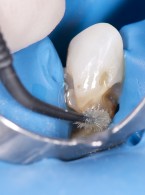

REPORTAŻ KLINICZNY. Bezpośrednia biomimetyczna odbudowa kompozytem zębów siecznych po urazie

Dawid Pisuk